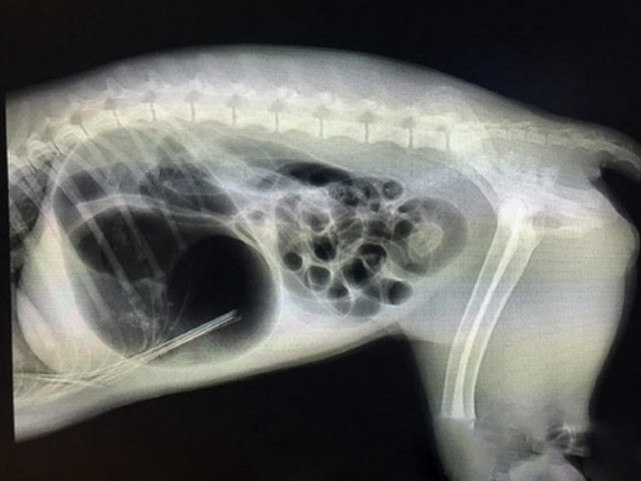

医生先跟狗狗照了一个X光片后,在X光片中并没有看见射到肚子里的箭损伤器官,于是医生们商量如何把这只箭从体内取出,如果太用力可能会导致狗狗的内部出血,而引起失血过多死亡。